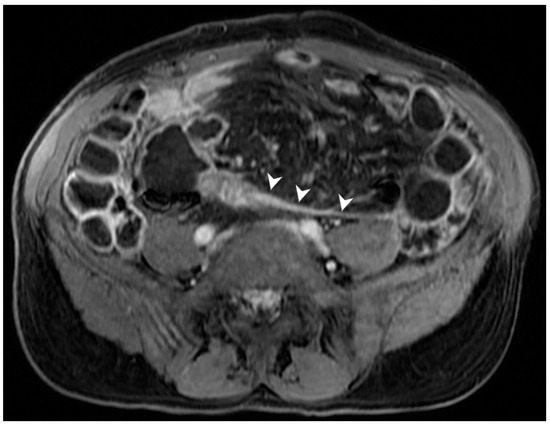

9. Is It Possible to Assess Post-Operative Recurrence?